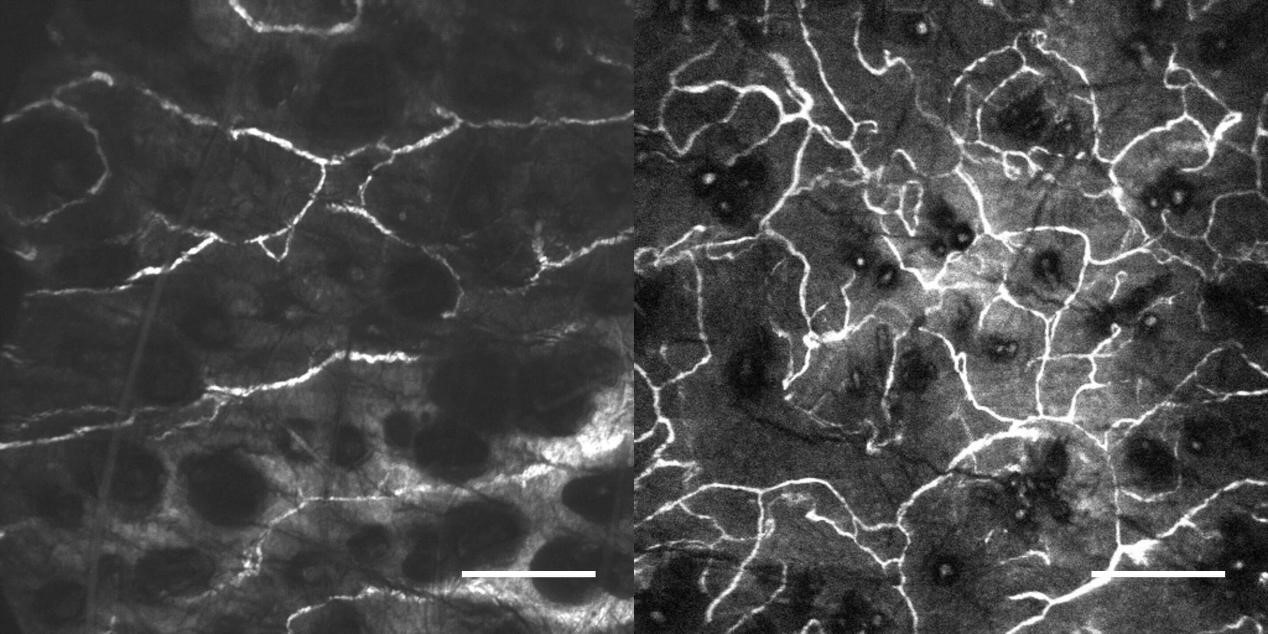

3、肿瘤血管生成OptiScan成像

左:正常皮肤微脉管系统;右:黑色素瘤影响的皮肤微脉管系统。

注:活体CLE成像显示无胸腺小鼠植入黑素瘤内及周围的黑素瘤相关脉管系统发生变化,静脉注射(0.3 ml, 10 mg / ml)fitc-葡聚糖作为造影剂。Scale bar=100μm。